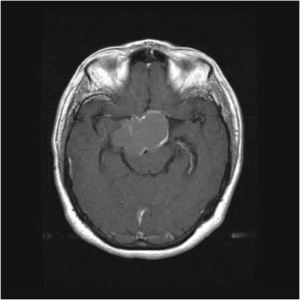

MRT-Bilder eines Kraniopharyngeom mit Druck auf die Sehnervenkreuzung (Chiasma).

Intraoperative Bilder einer Operation eines Kraniopharyngeom vor und nach Tumorentfernung mit freier Sehnervenkreuzung (Chiasma).